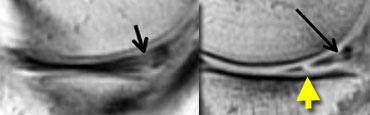

TRÁI: Phim MRI cũ có rách. Bệnh nhân đã được khâu phục hồi. PHẢI: Trên phim MRI mới, có rách mới (mũi tên vàng). Không thể xác định liệu vết rách cũ đã lành hay chưa.

Sụn chêm sau phẫu thuật 2

Bệnh nhân này đã được khâu phục hồi do rách sụn chêm.

Sau đó bệnh nhân bị chấn thương mới.

Trên phim MRI mới, không thể xác định liệu vết rách cũ đã lành hay chưa.

Tuy nhiên, phát hiện thấy rách mới, nên trường hợp này dễ chẩn đoán.

Chụp MRI-khớp: Tại vị trí rách mới, tín hiệu sáng tương đương dịch hoạt dịch (mũi tên vàng). Tại vị trí rách đã lành, tín hiệu không sáng bằng.

Trên ảnh chụp MRI-khớp, vị trí rách mới có cường độ tín hiệu rất cao tương đương dịch hoạt dịch, trong khi vị trí rách cũ đã lành chỉ có cường độ tín hiệu trung bình.

Do đó, so sánh với phim cũ giúp chẩn đoán xác định rách mới, trong khi ảnh chụp khớp cho thấy vết rách cũ đã lành.